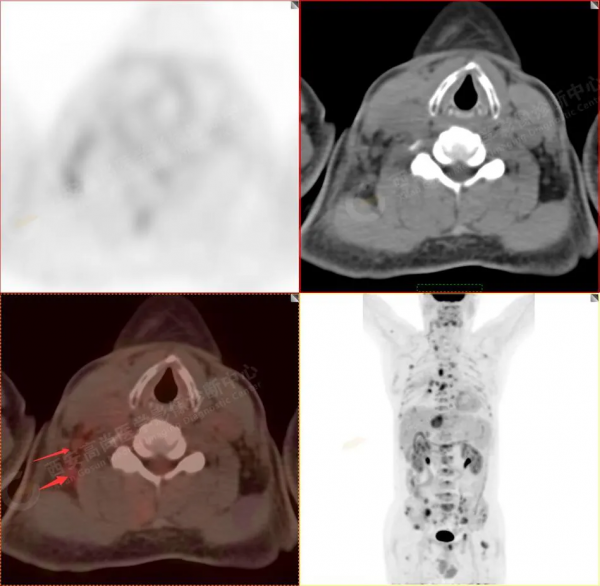

2.以下為部分全身多發轉移灶

2.雙肺多發高密度小結節灶(最大徑約0.7cm),部分較大結節呈FDG代謝略增高,均考慮為轉移性病變。

4.右後胸膜輕度增厚,形成多個條狀軟組織病變,呈FDG代謝輕度異常增高,考慮為轉移性病變;右側胸腔微量積液。

5.腰4椎體左側緣溶骨性骨質破壞,FDG代謝異常增高,考慮骨轉移瘤。